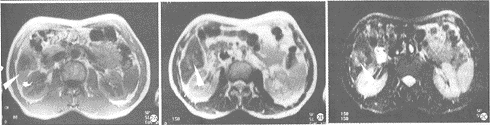

图2 肝右叶下段小HCC。A.SE-T1WI示癌肿为低信号,边清。

B.HASTE-T2WI示癌肿呈不均匀的略高信号,边缘欠清晰,癌肿的rCNR为0.42。

C.HASTE-IR-T2WI示癌肿呈高信号,边清,肿块的rCNR为1.10

图3 肝左叶小HCC。A.HASTE-T2WI示左叶内段小HCC呈稍高信号,边界尚清(↑)。

B.HASTE-IR-T2WI示左叶内段病灶为高信号,边清;

同时左叶外段还见到一直径约1mm大小的小HCC(↑)